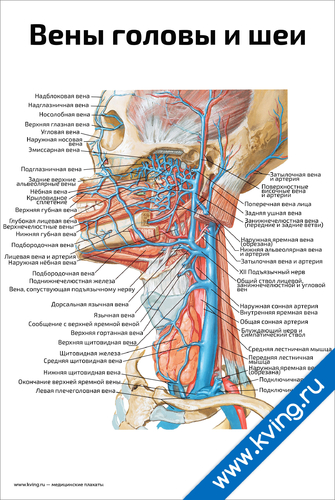

Анатомия внутренней яремной вены: КТ изображения